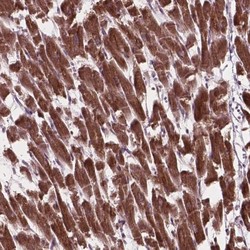

Immunohistochemistry

NBP2-49496 IHC